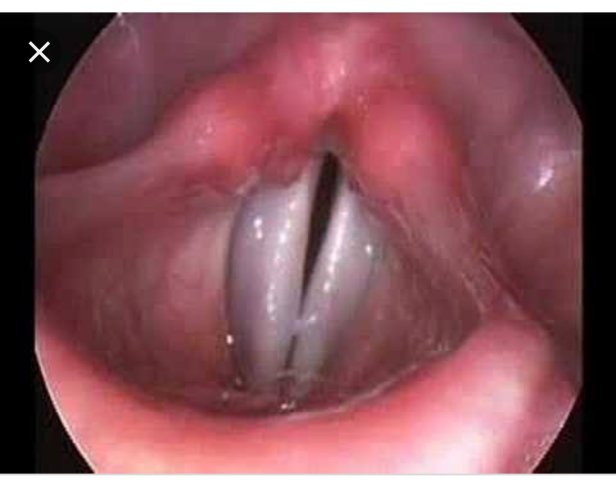

The fine art of placing the thin plastic tube between the elusive vocal cords in the throat and directly into the lungs, to assume the very big duty of breathing and keeping this human being alive. It’s a marvelous feat and a scary one too.

The vocal cords in my opinion deserve a sonnet, a poem, a story, an ode and a lengthy book just on its glorious beauty. Searching and digging in a persons throat with harsh metal equipment probably swished in blood and mucous, using the so called laryngoscope to find these 2 delicate marble wings fluttering behind the epiglottis. Open and closed. Taunting you in the most beautiful paradoxical manner there is. Beyond the cords lie the lungs. All you see is the blackness of everything a person is.